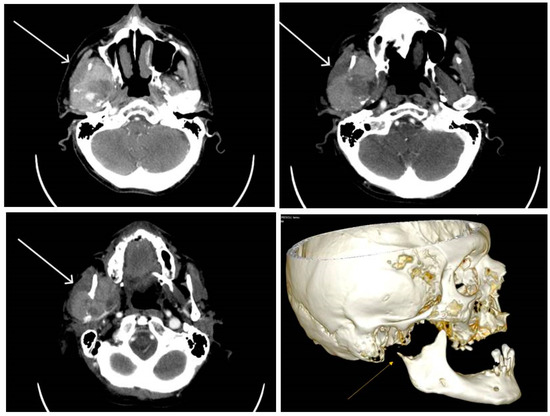

2.2.1. Clinical Findings

2.3.1. Clinical Findings